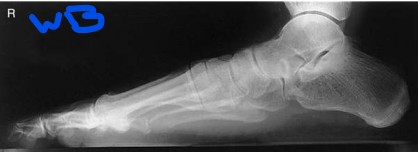

What is the evaluation criteria for a lateral foot projection?

entire foot demonstrated with 1 inch (2.5 cm) of distal tibfib. Heads of metatarsals are superimposed with the tuberosity of the fifth metatarsal base seen in profile

TRUE OR FALSE: the patient should carefully dorsiflex their foot if possible to assist in positioning for a lateral foot projection

TRUE

What anatomy is correctly demonstrated for a lateral WEIGHT bearing foot?

entire foot should be demonstrated along with 1 inch (2.5 cm) of distal tibfib. Distal fibula seen superimposed over posterior half of tibia, and plantar surfaces of heads of metatarsals should be superimposed if no rotation is present. The longitudinal arch of the foot must be demonstrated in its entirety

Name what anatomy is demonstrated in this projection of the foot